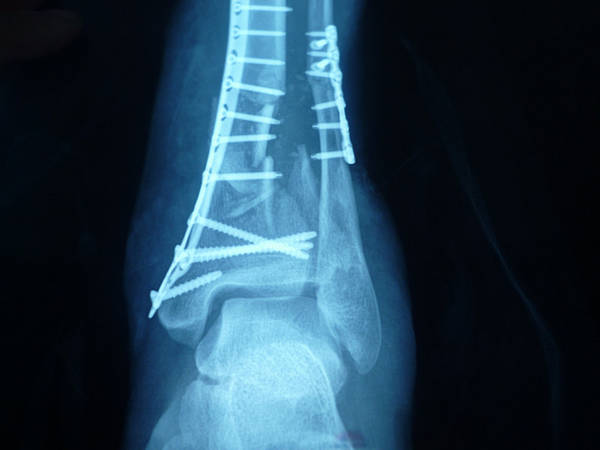

大家都是赞扬的,显微方面无可挑剔了。

骨折处理我来挑一下刺吧,

感觉骨量不够,

还有胫骨轴线欠佳了,

很可能发生创伤性关节炎,

当然做成这样已经不容易了,

能不能一期先植骨(或者同种异体骨?)

二期再行骨瓣移植,

请指教

又看了一次,要是不是遇到你,这个病人针要残疾了,一次手术解决下肢长短,局部软组织缺损及骨量缺失,为以后功能恢复提供了很好的条件,真的很牛牛牛牛牛牛牛牛牛牛